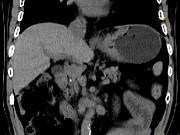

问题 男,75岁,吞咽有梗阻感,消瘦、乏力、中上腹痛,影像检查如图,最可能的诊断是()

选项 A.食道癌 B.胃窦癌 C.贲门癌 D.慢性胃炎 E.胃淋巴瘤

答案 C